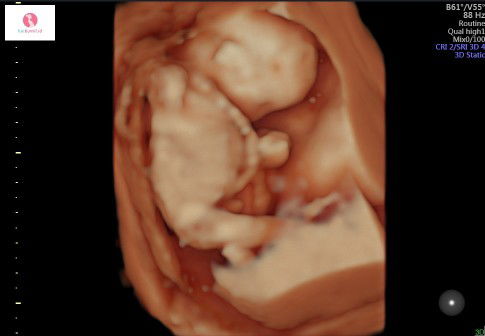

USG

Assalamualaikum buibu.... Alhamdulillah pass di USG tadi bayi ku sehat dan sudah terlihat jelas... Usia kandungan 3bulan 2 minggu??